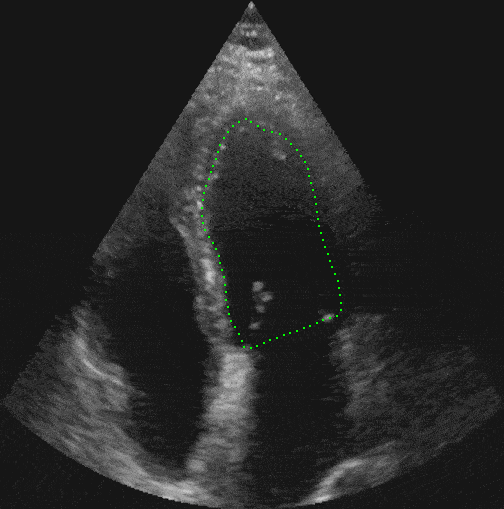

Automatic detection and measurement of the right atrium aids physicians to estimate the severity of pressure load or the existence of other pathologies. It is therefore key to provide the medical profession with a precise right atrium measurement tool. For this end, RSIP Vision has constructed software which automatically measures the right atrium. The videos we have analyzed are in 4 chamber view, in which the heart shape changes throughout its cycle. The dynamic changes complicate the detection and tracking. RSIP Vision has overcome the challenges of dynamic heart view using advanced image processing methods to track deformable objects. Coupled with machine learning procedures we have produced an algorithm to accurately measure the shape and volume of the right atrium.